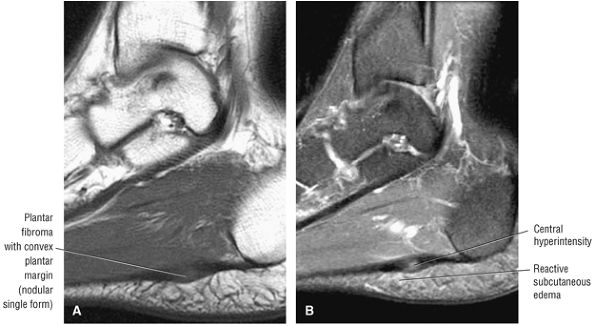

Inflamed synovium envelops the AITF and the inferior articulation of the tibia and fibula.

-

Synovitis may involve the anterior and posterior aspects of the syndesmotic ligament.

There may be associated loose bodies, chondromalacia, and osteophytes.

Bassett's ligament is a separate distal fascicle of the AITF and may be associated with syndesmotic impingement against the lateral talus.

and the lateral malleolus is pulled superiorly when the fibula is rotated medially (Fig. 5.219).